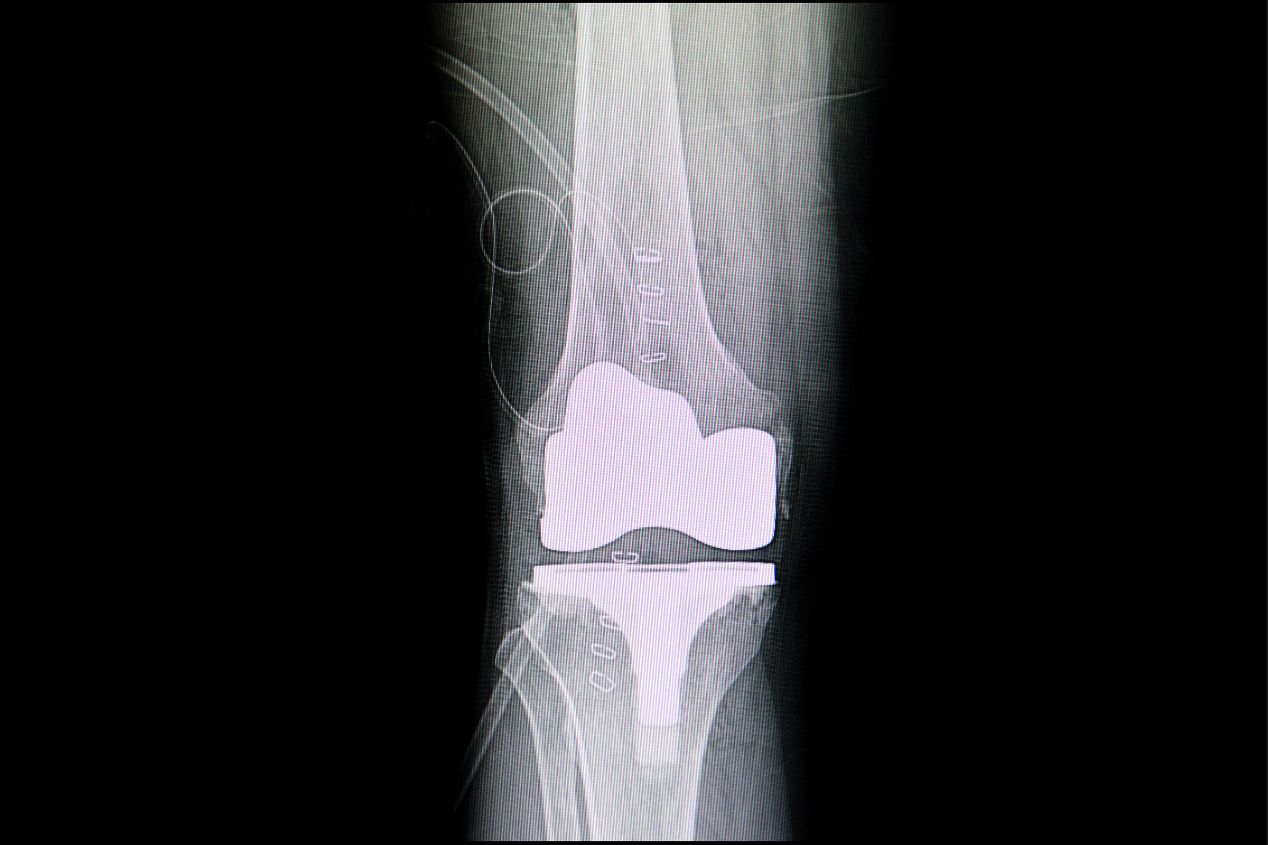

Πότε πρέπει να γίνει αρθροπλαστική γόνατος; Γιατί αξίζει να κάνει κανείς πραγματική ρομποτική αρθροπλαστική γόνατος;

Η αρθροπλαστική του γόνατος είναι μια χειρουργική επέμβαση που εκτελείται για την αντικατάσταση της φυσικής άρθρωσης  του γόνατος που έχουμε με μια τεχνητή  επιφάνεια άρθρωσης. Αυτή η νέα άρθρωση η οποία αποτελείται από υψηλής ποιότητας τιτάνιο εφαρμόζει απόλυτα στην υπάρχουσα αρθρική επιφάνεια. Πότε πρέπει να γίνει αρθροπλαστική γόνατος; Αδυναμία κίνησης: Όταν το γόνατο περιορίζει σημαντικά την κίνηση και την ελευθερία κινήσεων σας, προκαλώντας πόνο και δυσκολία στις καθημερινές δραστηριότητές. Πρέπει να αναφερθεί ότι η λογική η επέμβαση να γίνει όσο είναι δυνατόν σε μεγαλύτερη ηλικία λόγω περιορισμένου χρόνου ζωής των εμφυτευμάτων είναι παρωχημένη και δεν ισχύει για δύο λόγους.  Πρώτον η ζωή των εμφυτευμάτων έχει πολλαπλασιαστεί και δεύτερον δεν πρέπει να χάνει ο ασθενής τα όμορφα χρόνια της ζωής του με πόνο και δυσκινησία στην 5η 6η  7η΄ ή 8η  δεκαετία της ζωής του περιμένοντας την επέμβαση αλλαγής άρθρωσης.   Αν συμβαίνουν κάποιο από τα παρακάτω ζητήστε βοήθεια από εξειδικευμένο ορθοπαιδικό χειρουργό στις αρθροπλαστικές γόνατος ισχίου και να είναι ενημερωμένος και πιστοποιημένος  στις σύγχρονες τεχνολογίες.   Σοβαρός πόνος: Αν το γόνατο σας προκαλεί συνεχή, σοβαρό περιοριστικό πόνο που δεν αντιμετωπίζεται αποτελεσματικά με φαρμακευτική θεραπεία ή φυσικοθεραπεία. Σημαντική απώλεια λειτουργίας: Αν το γόνατο σας έχει υποστεί σημαντική απώλεια λειτουργίας, που επηρεάζει την ικανότητά σας να περπατάτε, να ανεβαίνετε σκάλες, ή να ασκείστε βασικές καθημερινές δραστηριότητες. Σοβαρή βλάβη στον χόνδρο ή παραμόρφωση.  Η απώλεια χόνδρου ή η σοβαρή φθορά στον χόνδρο στο γόνατο λόγω τραυματισμού ή αρθρίτιδας και παρουσιάζει παραμόρφωση όπως να είναι στραβό και να μην ανοίγει  πλήρως. Αποτυχία άλλων θεραπευτικών μεθόδων: Εάν άλλες μη χειρουργικές θεραπείες όπως φαρμακευτική αγωγή, φυσικοθεραπεία και απώλεια βάρους δεν έχουν δώσει αποτελέσματα και τα προβλήματα στο γόνατο συνεχίζουν να υφίστανται. Εάν ο πόνος ή ο περιορισμός κινητικότητας έχουν αρχίσει να επηρεάζουν αρνητικά την ψυχική κατάσταση και ο ασθενής έχει την τάση να αποσύρεται από δραστηριότητες που άλλοτε έκανε.   Η απόφαση για αρθροπλαστική γόνατος πρέπει να ληφθεί σε συνεννόηση με έναν εξειδικευμένο στις αρθροπλαστικές ορθοπεδικό χειρουργό πιστοποιημένο στην ρομποτική αν είναι δυνατόν ο οποίος θα αξιολογήσει την κατάσταση του γόνατος σας και θα σας συμβουλέψει σχετικά με τα οφέλη της επέμβασης. Η αρθροπλαστική γόνατος μπορεί να βελτιώσει σημαντικά την ποιότητα ζωής σας εάν υπάρχουν κατάλληλες ενδείξεις για αυτήν τη χειρουργική επέμβαση.   Γιατί αξίζει να γίνει ρομποτικά η αρθροπλαστική γόνατος:  Σε αυτήν την απόλυτη εφαρμογή παίζει ιδιαίτερα σημαντικό ρόλο η ρομποτική τεχνολογία στην αρθροπλαστική γόνατος. Η ρομποτική τεχνολογία βοηθάει τον χειρουργό να επιτύχει ένα πραγματικά άριστο αποτέλεσμα σε τρία στάδια.   Εξαιρετικά ακριβές πλάνο με βάση την εξατομικευμένη ανατομία με την χρήση ειδικής αξονικής τομογραφίας που γίνεται με τομές 0,6 χιλιοστών. Εικονική επιπροβολή εκθεμάτων (virtual implant superimpose). Αυτή η δυνατότητα υπάρχει μόνο στη ρομποτική τεχνολογία MAKO Stryker  που άλλωστε είναι και η μόνη καταξιωμένη υπάρχουσα ρομποτική μέθοδος. Αυτή η δυνατότητα επιτρέπει στον εξειδικευμένο πιστοποιημένο ορθοπαιδικό χειρουργό να δει συγχρόνως την ανατομία του ασθενούς με μεγάλη λεπτομέρεια σε συνδυασμό με τα εμφυτεύματα τιτανίου.  Με αυτόν το τρόπο μπορούμε να βρούμε το ένα και μοναδικό σημείο άριστης τοποθέτησης. Κατά τη διάρκεια της επέμβασης ο πιστοποιημένος εξειδικευμένος ρομποτικός ορθοπαιδικός χειρουργός βλέποντας τις δυναμικές συνθήκες ισορροπίας  στο γόνατο μπορεί να αλλάξει τα στοιχεία της προετοιμασίας της νέας άρθρωσης κατά κλάσμα του χιλιοστού για να επιτύχει ένα πραγματικά άριστο αποτέλεσμα. Μετά το τέλος τοποθέτησης των εμφυτευμάτων καταγράφουμε τα δυναμικά στοιχεία του γόνατος όπως ραιβότητα βλαισότητα σύγκαμψη και υπερέκταση ούτως  ώστε να δούμε αν πραγματικά έχουμε επιτύχει αυτό πού έχουμε σχεδιάσει. Πιστοποίηση από την εταιρεία ρομποτικής των ΗΠΑ ότι όντως έχει γίνει ρομποτική επέμβαση μαζί με πρόσβαση του ασθενούς στις μηχανικές ιδιότητες του γόνατος ή του ισχίου πριν και μετά την επέμβαση.   Είναι πλέον βέβαιο ότι τα αποτελέσματα της ρομποτικής αρθροπλαστικής στο γόνατο και στο ισχίο είναι ασύγκριτα καλύτερα.  1200 κορυφαία νοσοκομεία των ΗΠΑ μεταξύ των οποίων το Hospital for Special Surgery  (HSS)  Η Mayo Clinic το Mass General  έχουν και χρησιμοποιούν το μοναδικό στο είδος του σύστημα Robotic Arm Assisted Stryker. Είναι πολύ σημαντικό να γνωρίζουμε ότι υπάρχει η δυνατότητα σε 2 νοσοκομεία της Αθήνας να έχει κάποιος το ίδιο ακριβώς αποτέλεσμα σαν να είχε πάει στα καλύτερα νοσοκομεία του κόσμου.